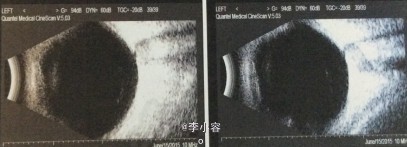

眼部检查: 视力:VOD:0.6 ,VOS:0.7,IOP:OD 45.4mmHg,OS 12.0mmHg,右眼结膜无充血,角膜透明,中央前房深度2CT,周边裂隙状,虹膜未见萎缩,瞳孔5×5mm,晶体混浊,眼底C/D=0.95,左眼结膜无充血,角膜清,中央前房深度2CT、周边裂隙状,瞳孔大小正常,晶体混浊,眼底C/D=0.5。 房角:右眼:N4(全粘闭) 左眼:N4(粘闭<1/2)

双眼原发性慢性闭角型青光眼(晚期 OD 早期 OS) .双眼老年性白内障 、 处理:右眼小梁切除术+前房成形术+虹膜周边切除术 左眼虹膜周边切除术

右眼视力0.5,眼压12mmHg滤过泡弥散隆起,2根可调缝线在位,角膜透明,ACD=3.5CT,PACD=1/4CT,房水细胞(+),虹膜周切口通畅,瞳孔约5×5mm,晶体混浊,眼底网膜平伏,C/D=0.95。 左眼结膜切口对合好,角膜透明,ACD=3.5CT,PACD=1/4CT,房水细胞(+),虹膜周切口畅,瞳孔3×3mm,对光反射存在,晶体混浊,眼底网膜平伏,C/D=0.5。 讨论:晶体因素导致的瞳孔阻滞是原发性慢性闭角型青光眼发病的主要诱因,包括晶体较厚,前、后表面曲率较大和相对位置偏前、虹膜晶体接触距离较大等. 病人常常具有眼轴短、前房浅的特点,容易发生房角粘连.视野缺损的程度与房角粘连程度成正相关,房角粘连范围愈广,视野缺损倾向愈大.眼压也与房角粘连程度成正相关,粘连的范围愈大,眼压值趋向愈高.提示房角粘连是慢闭发展的重要因素.虹膜周边激光切开术和小梁切除联合虹膜根部切除术都可以改善前房深度,但房角粘连范围大于180 °时,小梁切除术效果更明确,虹膜周边激光切开相对无效.